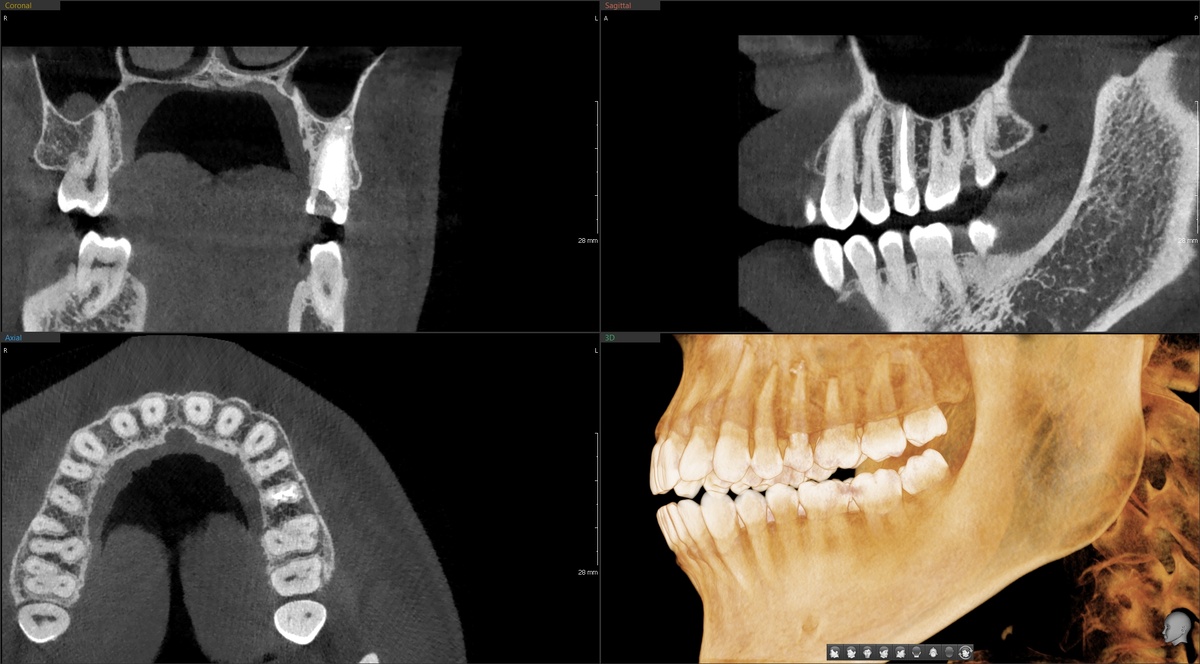

Перед приёмом сделали КТ. Это трёхмерный снимок, который показывает зубы и кости со всех сторон, в разных плоскостях - 3Д. Обычный прицельный рентгеновский снимок не подходит, он плоскостной, не достаточно информативный.

Терапевт провёл подробную консультацию, внимательно изучил снимок. В беспокоящем зубе 1.5 обнаружился кариозный процесс, всё ожидаемо. Лечить, пломбировать - понятный план. Но терапевт - дотошный товарищ, он смотрит широко, оценивает не только проблемный зуб, с которым пациент обратился. И вот, на снимке обнаруживается ещё одна проблема:

Красный круг- кариес, периодонтит 2.5 зуба

Точно такой же зуб на противоположной стороне - 2.5, верхний левый второй премоляр. Визуализируется очаг деструкции у верхушки корня, выглядит это как тёмный ободок. Периодонтит и есть. Хронический воспалительный процесс, который планомерно разрушает кость вокруг корня. Зачастую, делает это тихо, незаметно, без острой боли вне обострений.